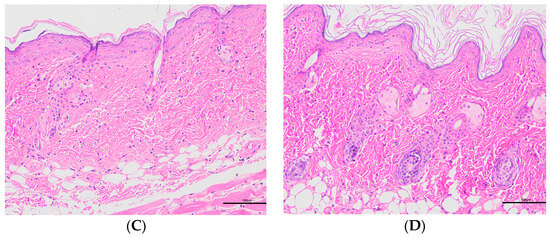

Histopathology was performed on the collected skin samples. Figure 10 shows the histopathological images of different groups. Histopathology sections showed that the epidermal layers of the skin of normal mice were thin and composed of one to two layers of epidermal cells (Figure 10A) [28,29,30]. In contrast to the normal group, the model group exhibited the abundant abnormal proliferation of SC cells and poor keratinisation, resulting in severe parakeratosis (Figure 10B). The data demonstrated that the skin structure was intact and normal for the Tre-FAV and Tre solution (Figure 10C,D). In the Tre-FAV group, there was a thickening of the stratum corneum, but it was not obvious, and the number of infiltrating inflammatory cells was also much less than that of the model group. This indicates that the prepared Tre-FAV has a good anti-psoriasis effect on psoriasis.

Figure 10.

Histopathological observation of skin lesions of mice in each group (HE × 200). Normal mouse tissue section observation (A), model mouse tissue section observation (B), Tre solution treatment group section observation (C) and Tre-FAV treatment group mouse tissue section observation (D).